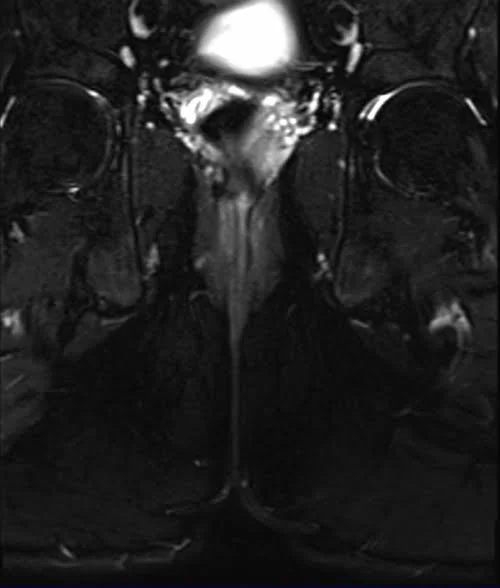

LUMBOSACRAL PLEXUS